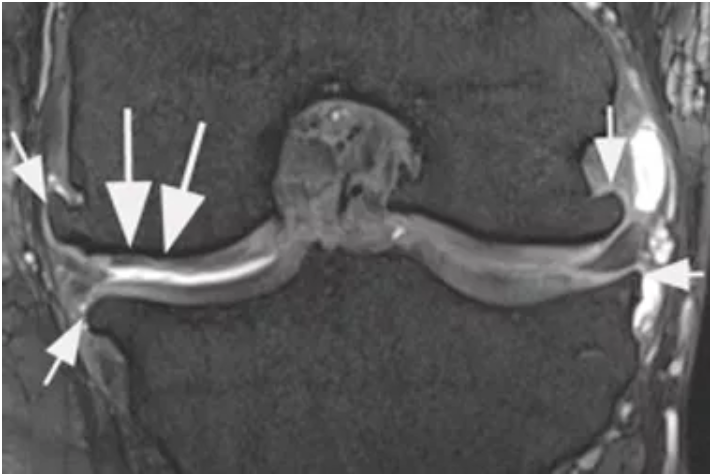

Multi-tissue assessment

Coronal dual echo at steady state (DESS) image shows 24 months follow up examination after MACI of the medial weight bearing femur (large arrows). Partial underfilling of the repair zone is noted. In addition large marginal osteophytes characteristic of definite osteoarthritis are noted at the medial and lateral tibio-femorla joint (small arrows). These osseous bone outgrowths are not assessed in grading schemes focusing on the repair zone only.